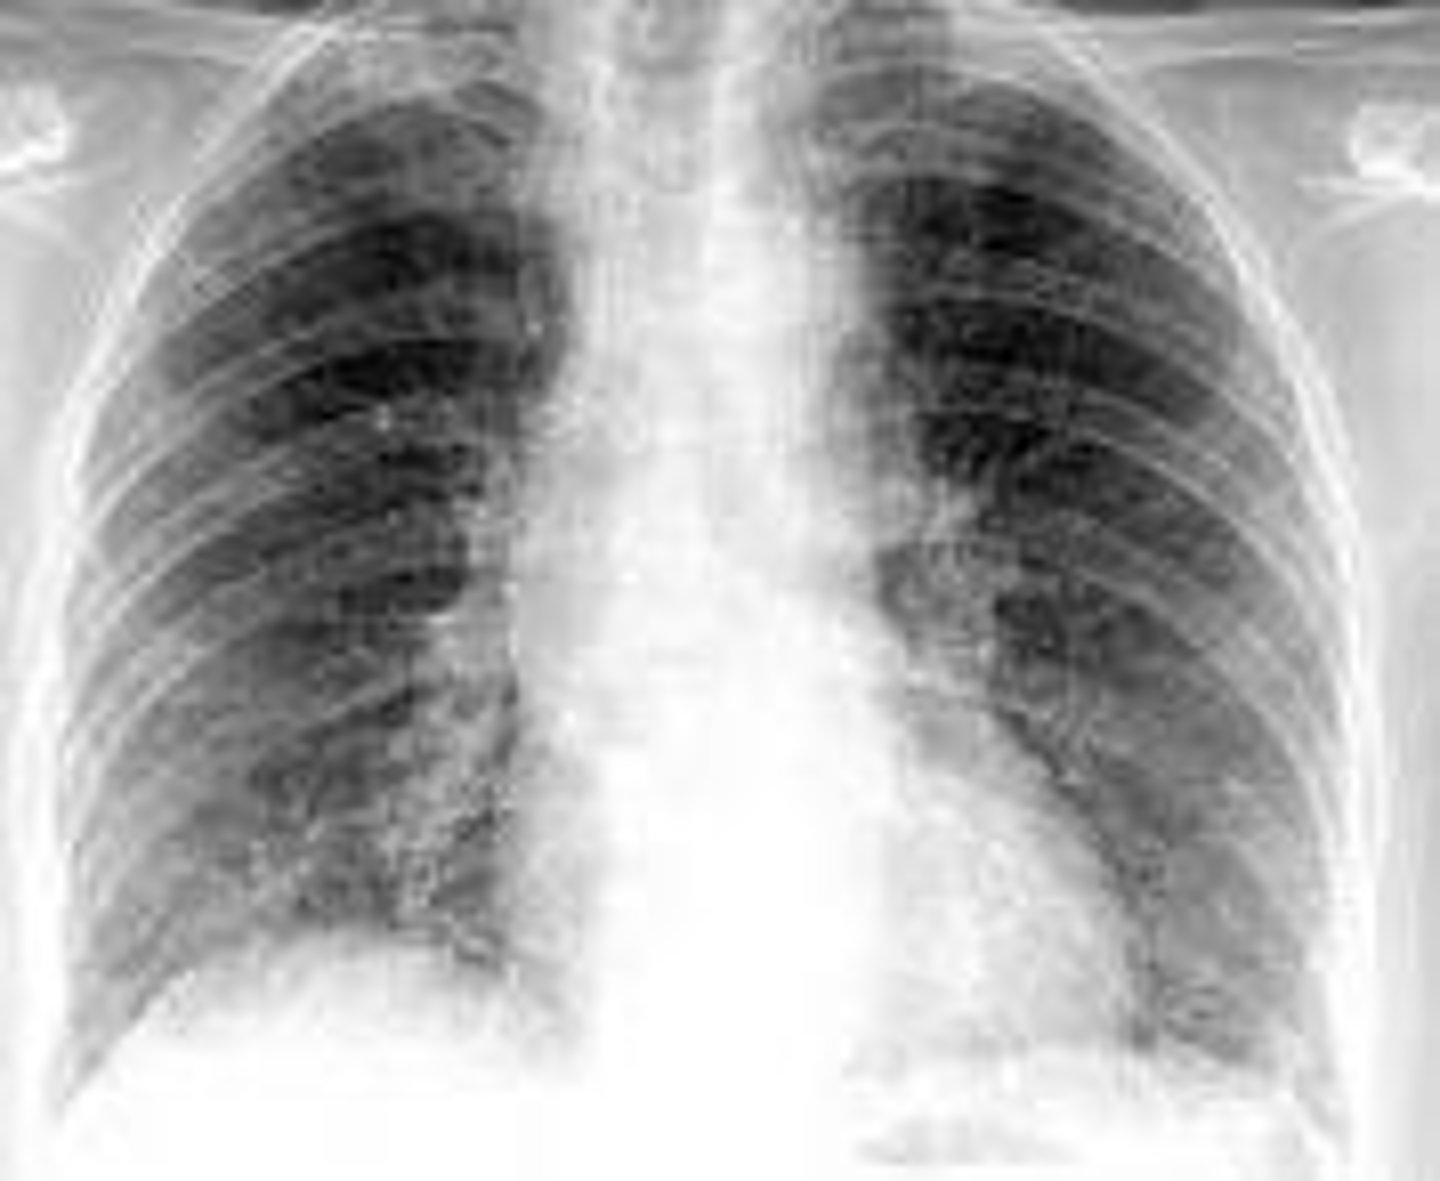

Atypical (walking) Pneumonia

Pathogen: Mycoplasma pneumoniae

S+S: Inflammation of the alveoli in one or both lungs --> Slow onset of dry cough and mild fever, NO chest pain/dyspnea

X-Ray: Look worse than symptoms - interstitial involvement

Transmission: Inhalation of/contact with infected oropharyngeal secretions